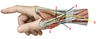

1? 2?

1: Levator scapulae muscle

2: Rhomboid major and minor muscles